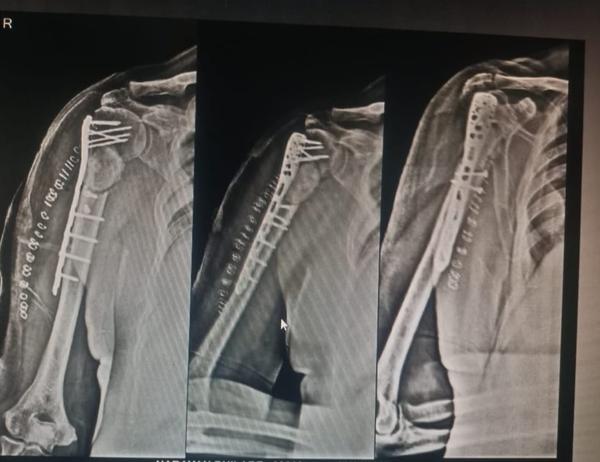

Fracture clavicle fixation with Locking anatomical clavicular plate !

View Details